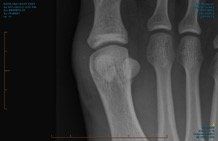

Sesamoid literally translates from a Latin word meaning seed, which is the shape of these two small bones in your foot. Located inside a tendon which lies under the first toe joint, these sesamoid bones serve a very important function during walking and running.

Medical imaging for this condition can include an x-ray, ultrasound, CT or MRI scan.